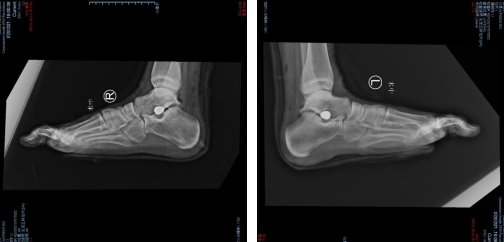

术前片

小敏来时正好遇上了俞光荣教授坐诊,俞光荣教授和曹广超主任一起给小敏做了检查,拍片显示小敏“双侧扁平足畸形”。

第二天,在完善的术前检查后,俞光荣教授曹广超主任王岩岩医生为小患者进行了双侧距下关节制动器植入及跟腱延长术,手术医生在患者双足跟腱表面合适位置取0.5厘米切口,分别进行了左右足的跟腱松解,将距下关节制动器置入距下关节,检查距下关节稳定,透视距骨头已抬高,meary角恢复正常。手术仅花了1小时,术中出血仅40ml,顺利完成。术后用石膏固定双侧脚踝保护跟腱。